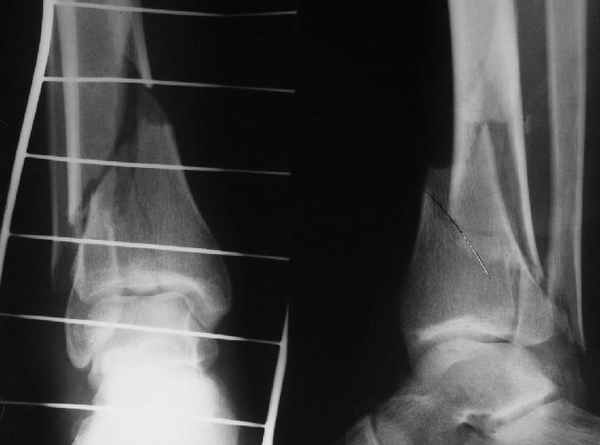

АЧ>если сопоставить стоимость отечественного гвоздика и пластины Synthes

Для значительной категории наших больных операции с применением имплантов SYNTHES и MATHYS - бесплатны, при производсвенной травме оплачивает ФСС, быт. травма,автодорожка при наличии полиса ДМС, разным льготникам часть ФОМС, а часть ад. города, причём для этих категорий АО - стандарт.

При штифтовании ортопедическим столом не пользуйтесь?